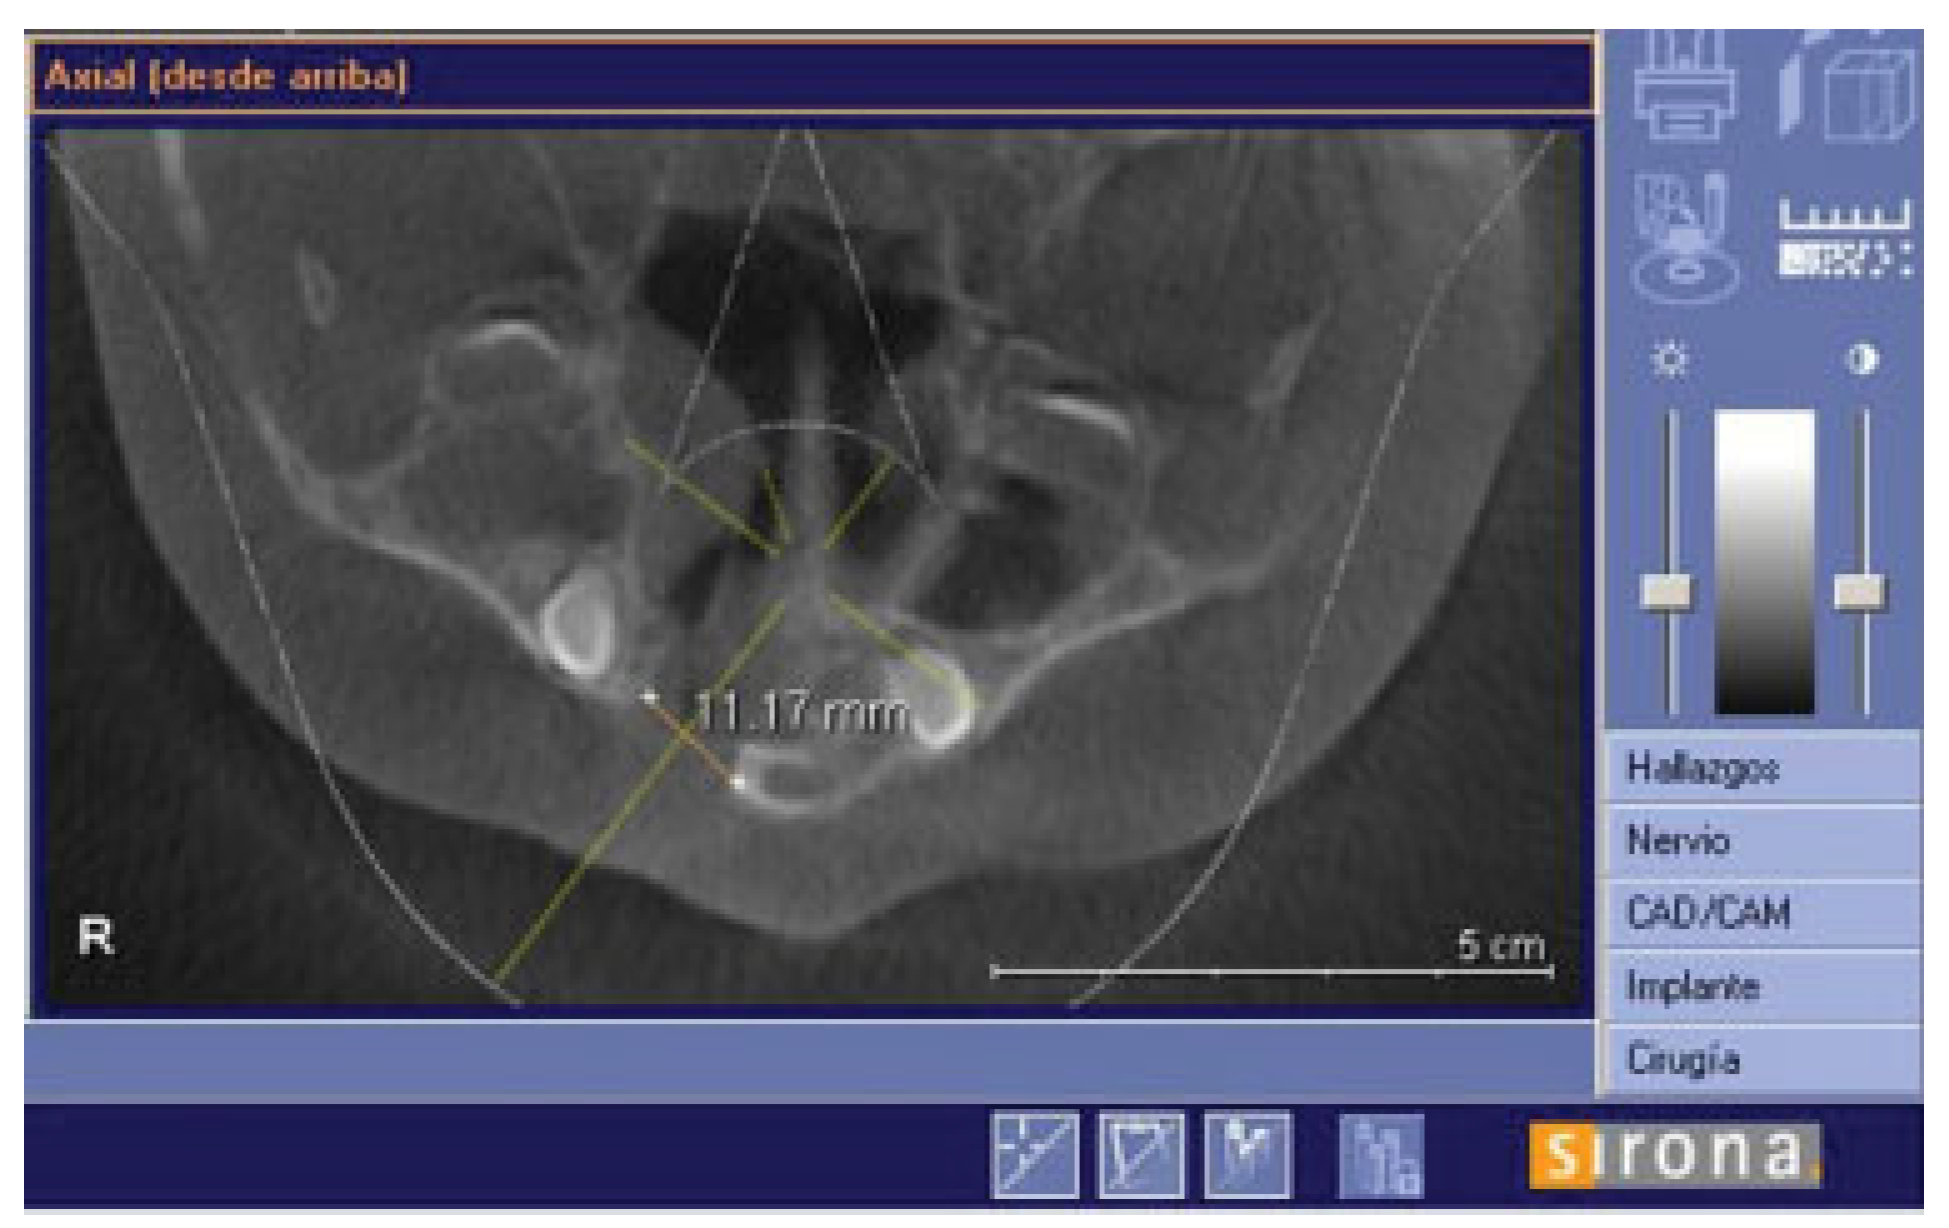

There were no intraoperative or postoperative complications. The fissure length in the upper edge when measured with a rule tool in the CBCT with Sirona Galileos software range from 5.76 to 16.93 mm (mean, 11.18 mm) (►Figure 4). All patients in the DBM group underwent a second CBCT assessment after 6 months of the surgical procedure. In the axial, coronal, and sagittal views and the three-dimensional reconstruction, there was no bone formation in none of the patients. The highest grayscale value in the area of the cleft was registered (►Figure 5), finding gray values between 1,148 and 1,496 (mean, 1,278.15). In our patients, the gray values corresponding to the bone adjacent to the cleft were higher than 1,504. During the follow-up performed 15 to 33 months postoperatively (mean, 28.2 months), occlusal and periapical X-ray were performed and analyzed by applying the Enemark scale; satisfying bone formation of 75% was observed only in just one patient. Four patients were reoperated with conventional surgery, using iliac crest grafts, because they need orthognathic surgery with Le Fort I osteotomy. At the time of reoperation, no bone formation was observed, although a crystallized material was seen in the pocket (►Figure 6) and was removed.

Figure 4.

Axial slide to show how the fissure was measured in the upper edge.

The CBCT was taken by the same team and machine, and studied in the Sirona Galileos software (Sirona Dental Systems, Long Island, NY); in the axial slides, a measurement was performed at the upper edge of the cleft; and during the follow-up (6 months postoperative), a new CBCT was taken to observe bone formation by the evaluation of the densities in the axial, coronal, and sagittal views of the cleft. The highest gray values in the cleft were recorded, and all patients continued their follow-up by plastic surgery and orthodontics. A CBCTwas not taken in the patients who underwent autologous grafts; these patients were followed up by periapical radiographs. Periapical radiographs were taken after at least 1 year of the surgery and were evaluated by Enemark scale, to calculate the percentage of ossification in the cleft area. Among other variables evaluated, we studied the eruption of the canine and the need for a second surgical procedure.